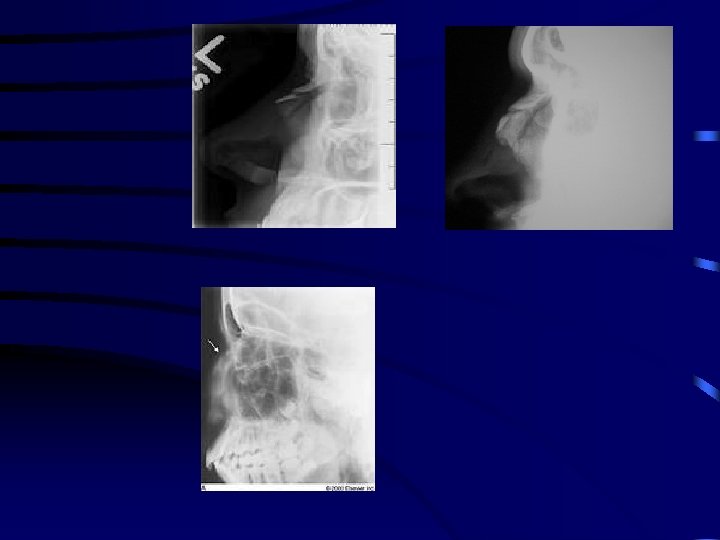

Maxillary fractures classification • Le fort 1 • Le Fort 2 • Le Fort 3

Le Fort 1

Le fort 2

Le Fort 3

Differentiating Le Forts Pull forward on maxillary teeth • Le Fort 1: maxilla only moves • Le Fort 2: maxilla & base of nose moves • Le Fort 3: whole face moves

Le Fort fractures signs and symptoms • • Epistaxis Circumorbital ecchymosis Facial oedema Surgical emphysema Infraorbital anaesthesia Anterior open bite ( in Le Fort 1&2) Haematoma at the junction of hard and soft palate